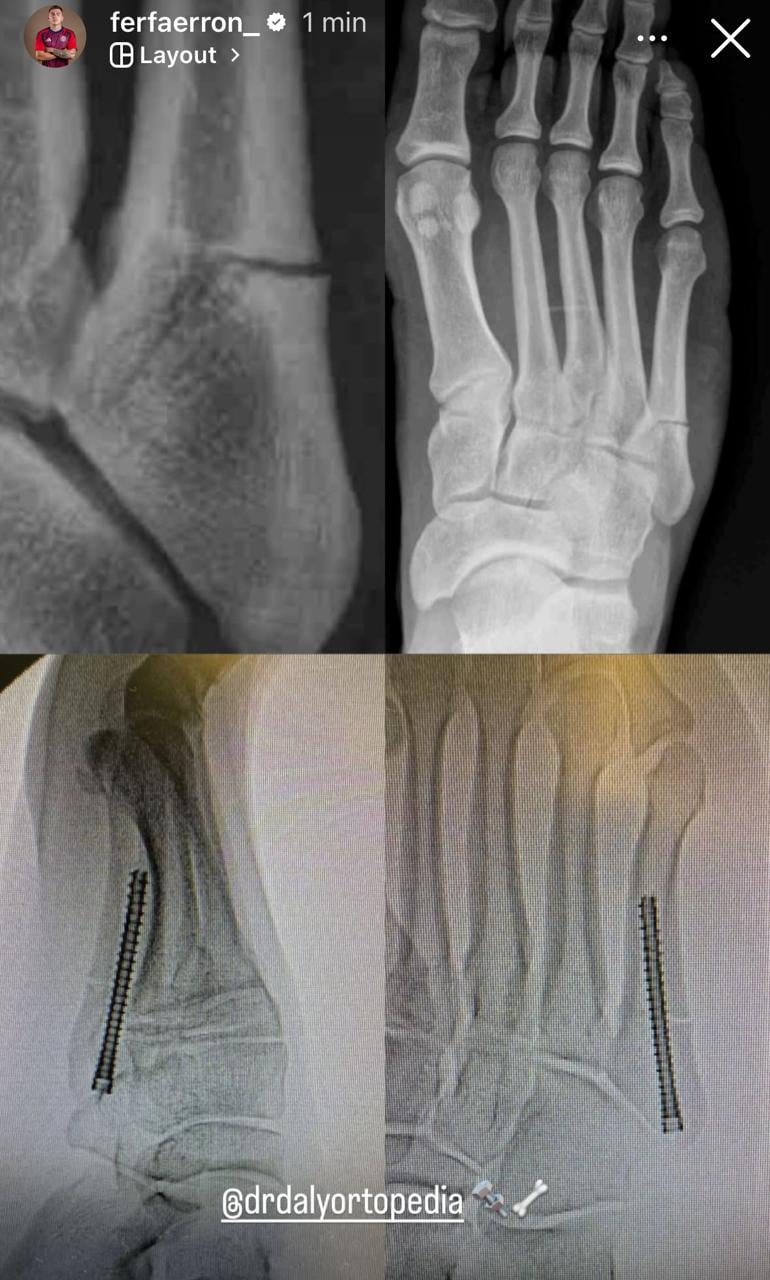

“Les informamos que el jugador Fernán Faerron fue operado con éxito tras una fractura del quinto metatarsiano en su pie izquierdo. El periodo de recuperación será evaluado acorde a su evolución en las próximas semanas”, comunicó el club.

El futbolista también mostró una fotografía de la intervención, donde se observa que el pin metálico que le colocaron en el pie.